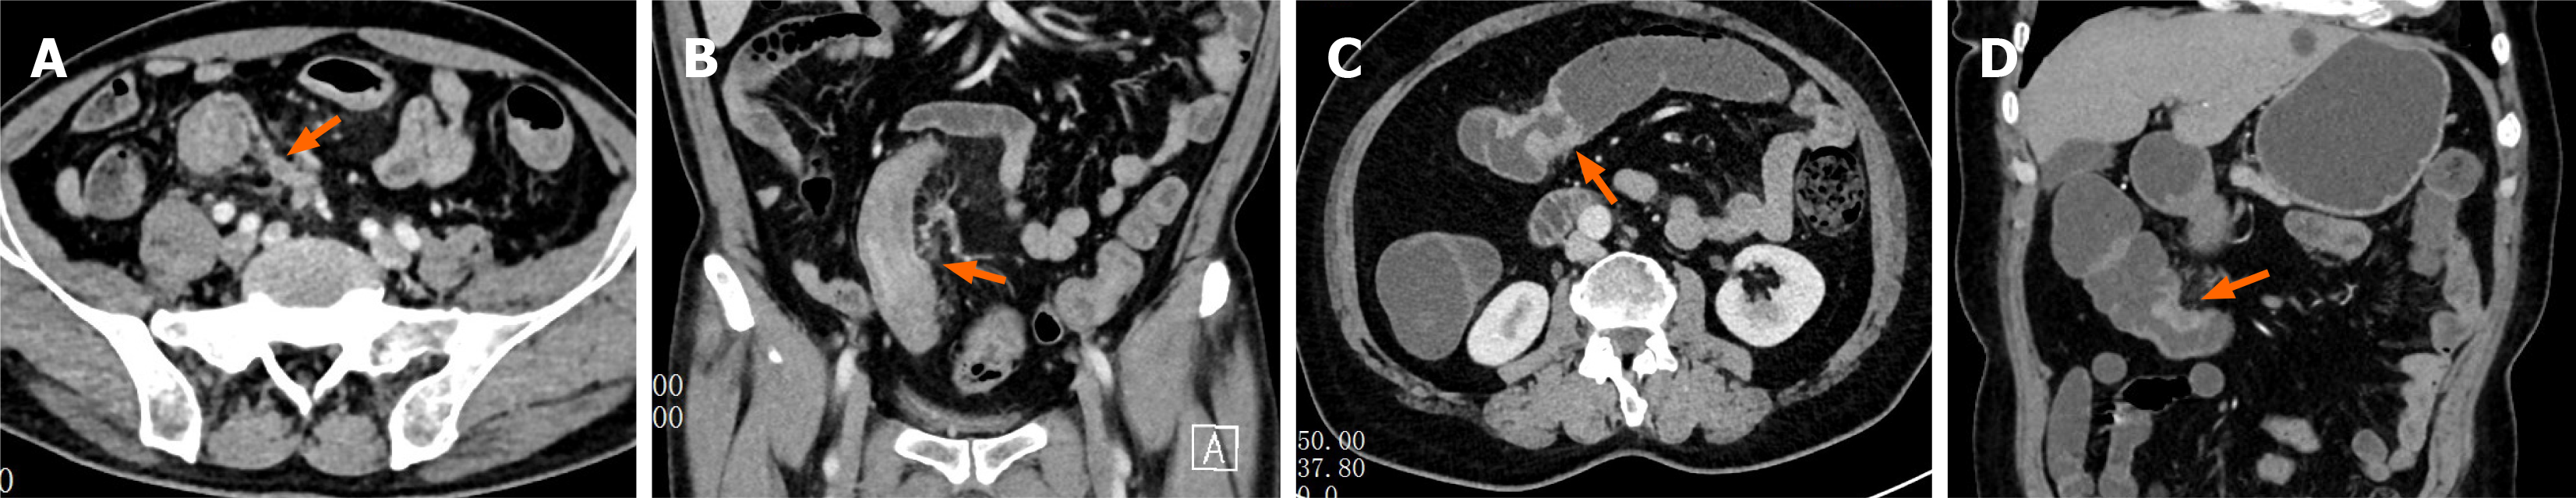

Figure 1 Computed tomography-detected extramural vascular invasion assessment of colon cancer patients.

A: Venous-phase axial computed tomography (CT) image demonstrates focal thickening of the sigmoid colon wall with blurred surrounding fat planes, enlarged adjacent extramural vessels with irregular contours, and intraluminal filling defects (arrow); B: Corresponding venous-phase coronal reconstructed image shows marked thickening of the sigmoid colon wall (arrow) and dilated, irregular extramural vessels containing intraluminal filling defects, consistent with CT-detected extramural vascular invasion-positive findings; C: Venous-phase axial CT image shows thickening of the transverse colon wall (arrow) with preserved surrounding fat planes; D: Corresponding venous-phase coronal reconstructed image demonstrates wall thickening of the transverse colon (arrow) without enlargement or irregularity of adjacent extramural vessels and without abnormal intraluminal density, consistent with CT-detected extramural vascular invasion-negative findings.